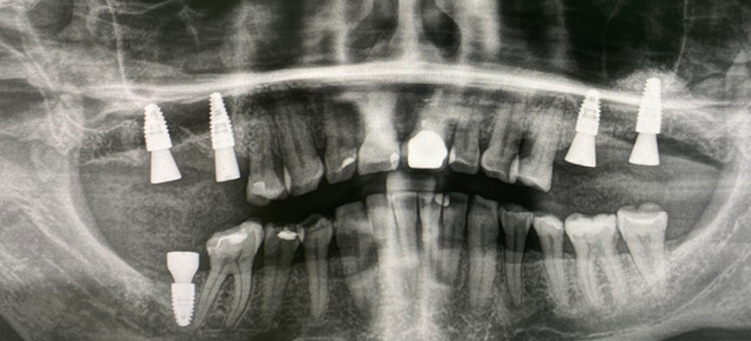

Установка имплантатов Straumann BLT